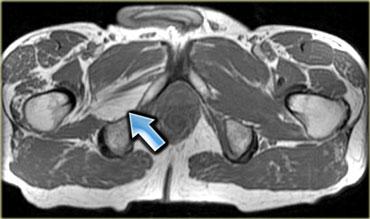

Hình bên trái là một ví dụ, lưu ý các thay đổi viêm ở các cơ lớn vùng mông.

Sau khi ngừng thuốc, đau cơ sẽ biến mất trong khoảng 2 tuần, tuy nhiên MRI vẫn còn cho thấy bất thường cho đến khoảng một tháng sau đó.

Thời điểm tốt nhất để chụp MRI theo dõi là khoảng 6 tuần sau khi ngừng thuốc.

Đây là bệnh nhân cao tuổi có tăng cholesterol máu được chỉ định dùng Lipitor.

Bệnh nhân xuất hiện đau nhức cơ, CPK tăng nhẹ.

Các thay đổi khá tinh tế, chúng ta thấy các ổ tụ dịch quanh mạc cơ, ở rìa ngoài của cơ (ngoại mạc cơ).

Ngoài ra còn có thay đổi da tối thiểu.